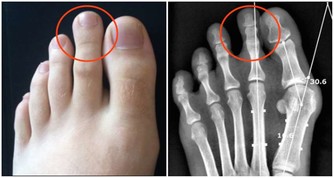

具體是怎麼做的呢?首先,坐下來伸直雙腿,將掌心按在髕骨上,從外往裡揉,揉38下,再從裡往外,揉38下。

然後,雙手分別抓住雙腿的髕骨,往上提38下。

接著,屈起雙腿,用手指同時按揉外膝眼、內膝眼,共38下。

“每天早上起床時,坐在床上屈膝揉一次,晚上睡覺前揉一次。堅持兩三個月,對關節健康很有好處。”